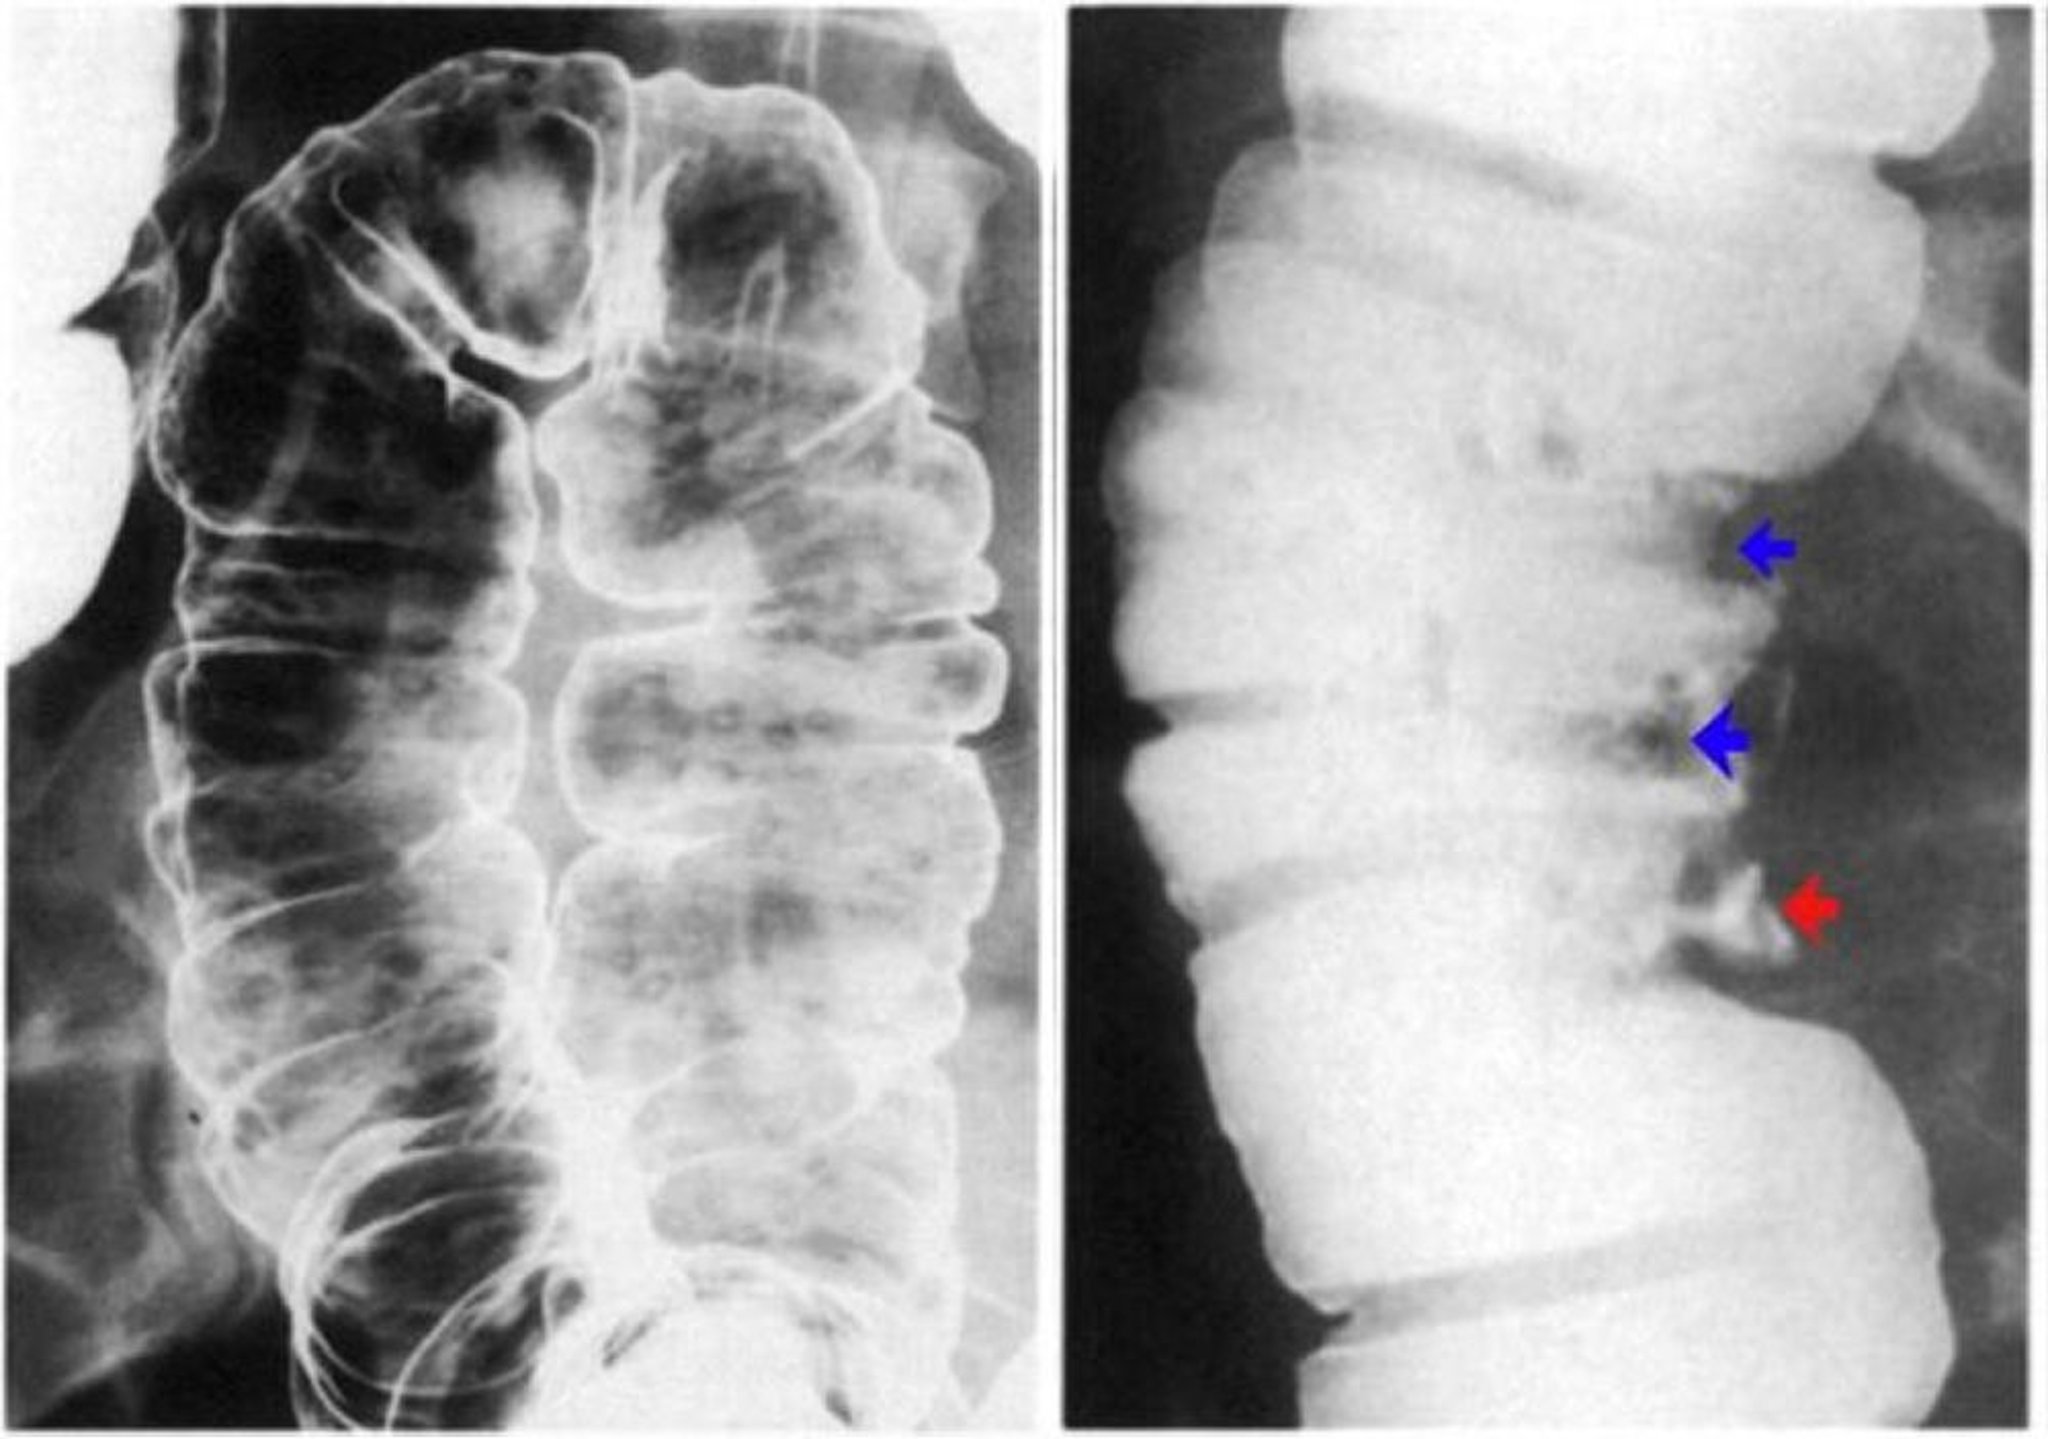

Clisma opaco con bario che mostra ulcerazione della parete del colon

L'immagine a sinistra mostra ulcere aftose. Ci sono erosioni discrete con un alone lucente su uno sfondo di mucosa normale. L'immagine a destra mostra pseudopolipi dimostrati da difetti di contrasto (frecce blu) e anche un'ulcera profonda (freccia rossa).